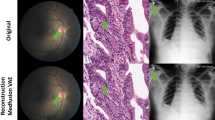

Generative latent diffusion models have been established as state-of-the-art in data generation. One promising application is generation of realistic synthetic medical imaging data for open data sharing without compromising patient privacy. Despite the promise, the capacity of such models to memorize sensitive patient training data and synthesize samples showing high resemblance to training data samples is relatively unexplored. Here, we assess the memorization capacity of 3D latent diffusion models on photon-counting coronary computed tomography angiography and knee magnetic resonance imaging datasets. To detect potential memorization of training samples, we utilize self-supervised models based on contrastive learning. Our results suggest that such latent diffusion models indeed memorize training data, and there is a dire need for devising strategies to mitigate memorization.